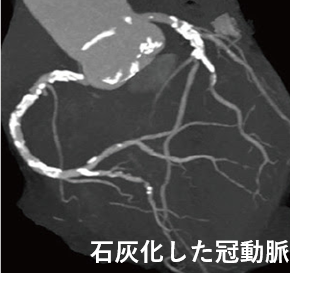

~心血管治療センター(冠動脈石灰化病変の治療)~

管の石灰化は、血管内に蓄積した脂質にカルシウム成分が沈着することで発生し、ご高齢の方や、高血圧、腎機能障害のある方にも多く見受けられる病態です。心臓に酸素や栄養を供給する冠動脈にできる石灰化は経皮的冠動脈形成術に用いられるバルーンカテーテルだけでは治療することが難しくなる場合も多く特殊な治療器具が必要になる事もあります。